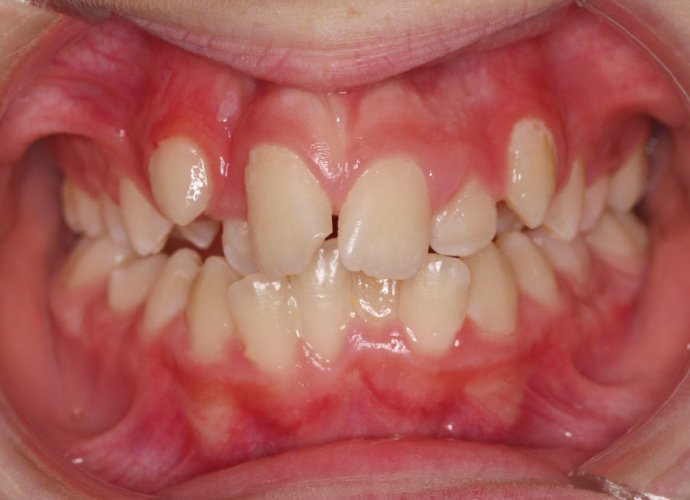

Un “diastema” es una separación extraordinariamente grande entre dos o más dientes. La mayoría de las veces, el diastema aparece entre los dos dientes delanteros superiores. Muchos niños tienen diastema cuando se les caen los dientes de leche, pero en la mayoría de los casos esta distancia desaparece cuando salen los dientes permanentes.

Los diastemas pueden deberse a una diferencia en los tamaños de los dientes, a la falta de algún diente o a que el frenillo labial sea demasiado grande. El frenillo labial es el tejido que va desde el interior del labio hasta la encía, en el lugar donde se sitúan los dos dientes delanteros superiores. Los diastemas también pueden deberse a problemas en la alineación de la boca, como la sobremordida horizontal o la protrusión de los dientes1.